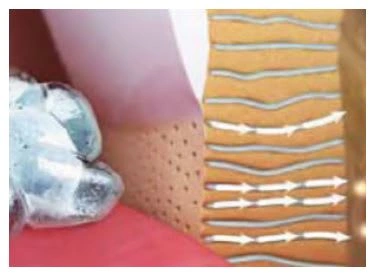

Dental erosion occurs primarily due to the excessive presence of non-bacterial extrinsic acids (especially dietary acids such as acidic drinks), as well as intrinsic gastric acid associated with gastroesophageal reflux disease (GERD) and bulimia (Moazzez et al. 2004; Bouqot & Seime 1997). Dental erosion involves the demineralization and softening of the tooth surface, which once softened, is highly susceptible to abrasion and attrition (Figure 7). A diagnosis of erosion can be made based on the pattern of surface loss of enamel and/or dentin (Figures 8a,b)

Figure 7. Demineralization associated with dental erosion

Figure 7. Demineralization associated with dental erosion